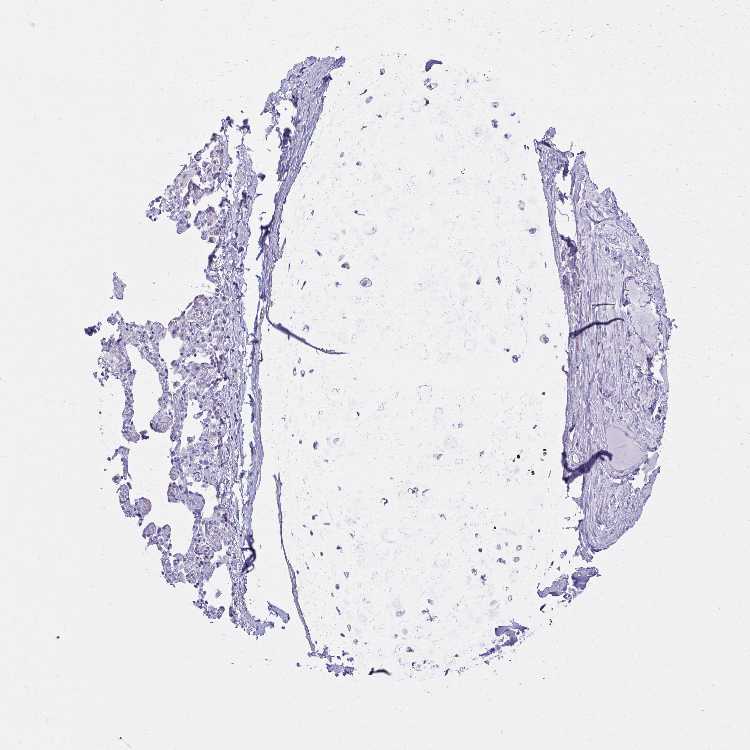

SOFT TISSUE 1 - Antibody stainingi

Antibody staining in the annotated cell types in the current human tissue is reported as not detected, low, medium, or high, based on conventional immunohistochemistry profiling in selected tissues. This score is based on the combination of the staining intensity and fraction of stained cells.

Each image is clickable and will lead to virtual microscopy that enables deeper exploration of all samples and also displays staining intensity scores, fraction scores and subcellular localization as well as patient and tissue information for each sample.

Antibody HPA056030Antibody HPA063513Antibody CAB000039

Chondrocytes Not detectedNot detected-

Fibroblasts Not detectedNot detectedNot detected

Peripheral nerve Not detectedNot detectedNot detected